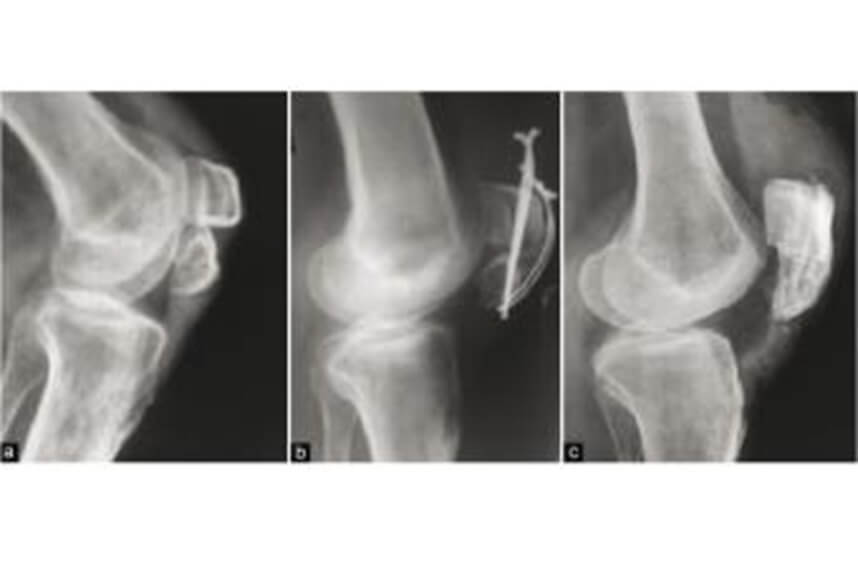

Fractura rotulei![]()

La acest tip de traumatism, durerea, inflamatia si limitarea miscarii genunchiului apar imediat.

Tratamentul conservativ de regula incepe cu imobilizare, apoi prin hidrokinetoterapie si gimnastica de recuperare cu scopul de a reduce durerea prin intarirea musculaturii.

Interventia chirurgicala poate fi necesara in cazul in care patela este fragmentata sau dislocata. In acest caz programul nostru post operator te ajuta sa te recuperezi complet intr-un interval de aproximativ 3 luni.